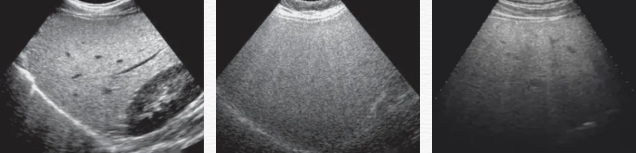

脂肪肝作为代谢综合征的一个重要组成部分,其发病率在全球范围内呈上升趋势,对人类健康构成严重威胁。早期诊断并及时治疗脂肪肝是防止疾病进展的关键。传统的超声成像(US)是一种广泛使用的筛查肝脏脂肪性改变的方法,通过肝脏实质回声、肝内血管及膈肌显示、远场衰减评估,但由于其对肝脏脂肪含量的估计是主观的,尤其在轻度脂肪变性的诊断中敏感性不高。因此,精准客观的脂肪肝检测法成研究重点,在此背景下,新型无创定量检测技术——高级声衰减定量成像技术(ATITM,Attenuation Imaging )应运而生。

声衰减定量成像技术的应用范围非常广泛,包括肝脏疾病、乳腺肿瘤鉴别、肾脏病变以及肌肉骨骼系统等多方面的病变。712a8084746869e803a3684e2526ee4.png肝脏疾病诊断在脂肪肝的评估中,脂肪作为一种声衰减介质,超声波在脂肪肝内的传播会产生衰减,肝脏中脂肪组织比例越大,超声衰减就越高。在肝硬化患者的肝脏中,肝脏组织的纤维化和结构改变会导致超声声衰减特性的改变。声衰减成像技术可以帮助医生观察肝脏实质的变化,辅助判断肝硬化的程度,同时对于监测肝硬化治疗过程中的病情变化也有一定的价值。